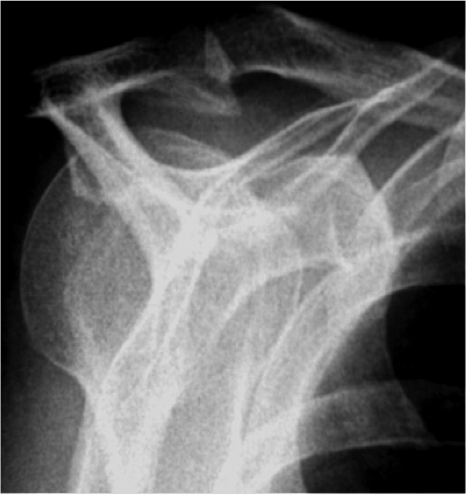

Schultergelenksluxation:

Das Schultergelenk besteht aus dem Oberarmkopf und der Gelenkpfanne. Die Stabilisierung des Gelenkes erfolgt durch die Gelenkkapsel, Sehnen und Muskeln sowie

einem knorpeligen Ring, den man als Labrum bezeichnet, der die Gelenkpfanne umgibt.

Die Ursachen von Luxationen des Schultergelenkes können anlagebedingt sein (z.B.

zu große Kapsel, schlaffer Bandapparat) oder sie sind Folgen von Verletzungen. Verletzungen wie z.B. Skistürze, bei denen das Schultergelenk sich ausrenkt, führen häufig zum Abriss des Labrums. Dadurch wird die Stabilität des Schultergelenkes dauerhaft gestört, so dass wiederholte Luxationen des Gelenkes

auftreten oder dass eine schmerzhafte Bewegungseinschränkung verbleibt. Hier ist eine operative Therapie vor allem bei jüngeren Patienten häufig unumgänglich.